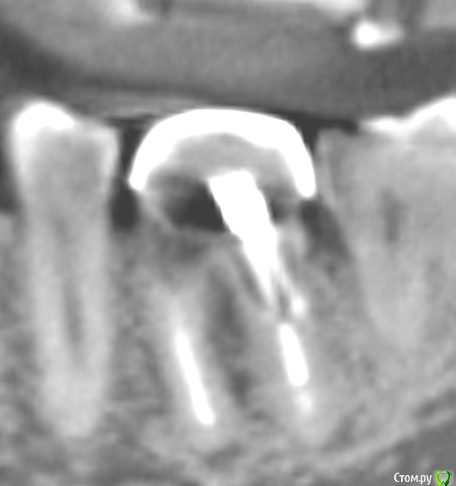

krokomot Опубликовано 26 февраля, 2015 Поделиться Опубликовано 26 февраля, 2015 Уважаемые коллеги есть сомнительный зуб который 10 лет разрушался под штампованной коронкой. Предложите варианты лечения, не учитывая эндодонтическое лечение. И стоит ли?! Всем спасибо за участие. после некрэктомии Щадящей! Ссылка на комментарий

krokomot Опубликовано 26 февраля, 2015 Автор Поделиться Опубликовано 26 февраля, 2015 Тем неменее перфорций стенок нет, полноценная только вестибулярная стенка разделения корней нет, устойчив. не беспокоил. Удалить проблем нет, как вы думаете возможно ли восстановление, если можно обосновывайте ответ. Хотел еще фото с внутри ротовой но ассистент удалил Ссылка на комментарий

chervoncevdaniil Опубликовано 26 февраля, 2015 Поделиться Опубликовано 26 февраля, 2015 Тем неменее перфорций стенок нет, полноценная только вестибулярная стенка разделения корней нет, устойчив. не беспокоил. Удалить проблем нет, как вы думаете возможно ли восстановление, если можно обосновывайте ответ. Хотел еще фото с внутри ротовой но ассистент удалил Док,дефект ниже уровня кости,очень тонкие стенки,некачественное эндо,феррула тут и в помине нет,какие еще аргументы нужны?целесообразность сохранения такого зуба какая? 2 Ссылка на комментарий

krokomot Опубликовано 26 февраля, 2015 Автор Поделиться Опубликовано 26 февраля, 2015 (изменено) Док,дефект ниже уровня кости,очень тонкие стенки,некачественное эндо,феррула тут и в помине нет,какие еще аргументы нужны?целесообразность сохранения такого зуба какая?Спасибо за поддержку) Просто у пациента как низуб так сюрприз, везде где было эндо все оч плохо кстати в моем посте про каналонаполнители в 3-х каналах тоже его зуб. Изменено 26 февраля, 2015 пользователем krokomot 2 Ссылка на комментарий

krokomot Опубликовано 27 февраля, 2015 Автор Поделиться Опубликовано 27 февраля, 2015 Удаляйте лучше. Зачем вам проблемы с этим пациентом в будущем?Обновлено. Добавляю недостающее фото удалил после повторной ревизии обнаружилась перфа на дистальной стенке, ниже уровня устья. 1 Ссылка на комментарий